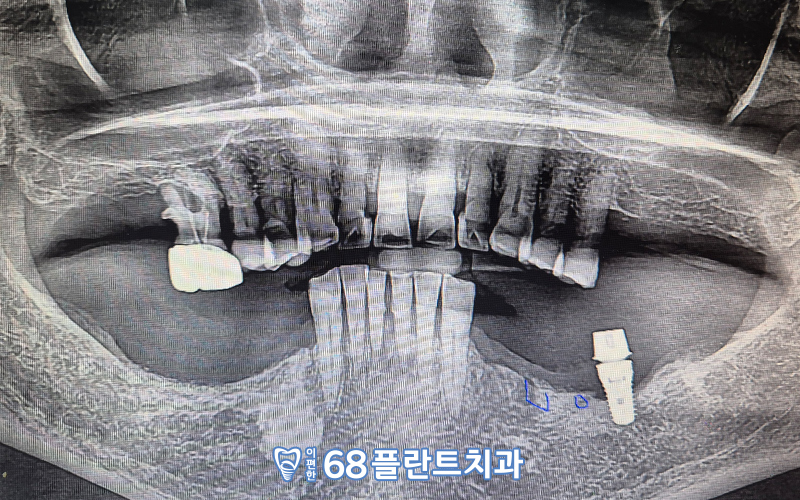

📌 파노라마 사진을 촬영해 체크해보니

어금니들이 거의 대부분 상실된 상태로

거의 앞쪽을 활용하여

식사를 하고 계신 상태였습니다.

📌 그리고 오른쪽 위의 가장 후방의 어금니는

신경치료 + 크라운 수복치료를 받은 치아로

잇몸뼈가 거의 녹아

치아가 흔들리는 상황이라 발치가 필요하였고,

📌 왼쪽 아래 어금니는 타원에서

임플란트 식립만 진행하였고

크라운(보철물)을 씌우는 작업은

아직 진행하지 않은 상태였습니다.